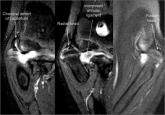

Structural failure of rotator cuff repairs has been attributed to multiple factors, including poor repair tissue quality and poor tendon–bone...